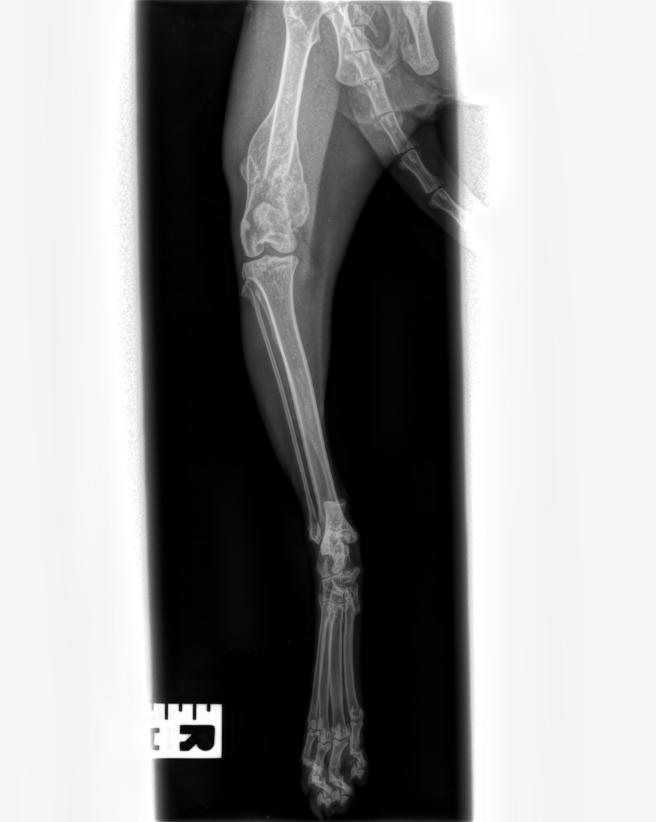

Luckily we managed to find a fosterer who could take care of Zendaya, a 2 year old tabby cat who was found in Park Hill Park in Croydon by members of the public. Her fosterer noticed in the first week that Zendaya was limping slightly. When we took her to the vets for a health check we made sure this was looked at too. It turned out that she had a healed femur fracture that likely occurred a few weeks prior!

Although the bone was healed, the broken parts weren’t aligned properly which has made her leg 1cm shorter than the other. The area was also likely to be more fragile, so the vets recommended that Zendaya be re-homed as an indoor cat.

She will have a second X-ray in late September to make sure the bony spur isn’t growing or causing any problems. This will be a further cost to us of £260 ahead of her adoption.